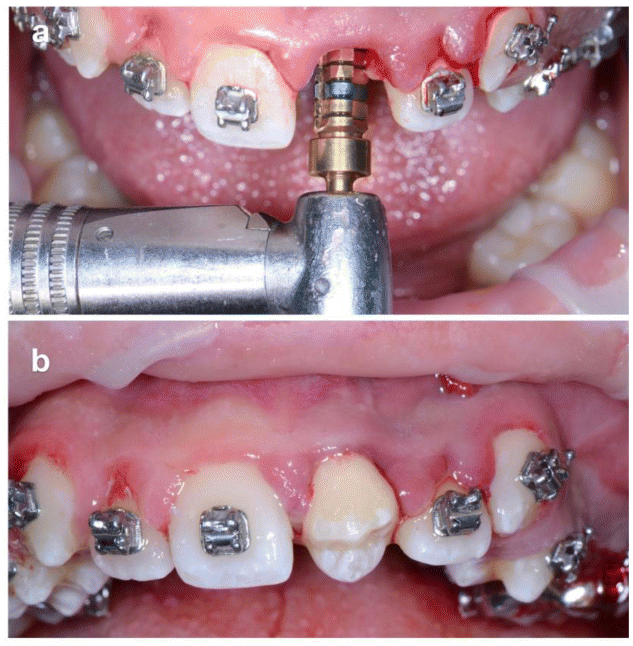

The donor tooth chosen was the maxillary left second premolar (2.5), which presented incomplete root development (Figure 3b). Following six weeks of orthodontic pre-treatment to mobilize and stimulate periodontal tissues (Figure 3), surgical extraction of 2.1 was performed under local anesthesia (Figure 4).

The socket was prepared using implant drills according to the dimensions of the donor tooth (Figure 5a). Tooth 2.5 was atraumatically explanted, immediately transplanted into the 2.1 site (Figure 5b), and stabilized passively with a flexible orthodontic splint. Coronoplasty was performed to avoid occlusal interference.